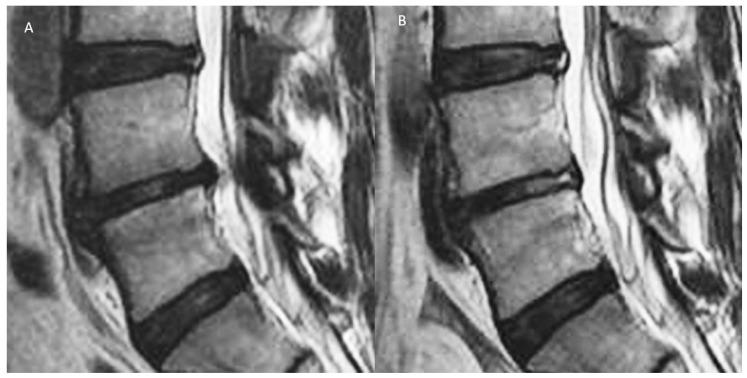

Intervertebral Disc Diseases PART 2: A Review of the Current Diagnostic and Treatment Strategies for Intervertebral Disc Disease.

With an aging population, there is a proportional increase in the prevalence of intervertebral disc diseases. Intervertebral disc diseases are the leading cause of lower back pain and disability. With a high prevalence of asymptomatic intervertebral disc diseases, there is a need for accurate diagnosis, which is key to management. A thorough understanding of the pathophysiology and clinical manifestation aids in understanding the natural history of these conditions. Recent developments in radiological and biomarker investigations have potential to provide noninvasive alternatives to the gold standard, invasive discogram. There is a large volume of literature on the management of intervertebral disc diseases, which we categorized into five headings: (a) Relief of pain by conservative management, (b) restorative treatment by molecular therapy, (c) reconstructive treatment by percutaneous intervertebral disc techniques, (d) relieving compression and replacement surgery, and (e) rigid fusion surgery. This review article aims to provide an overview on various current diagnostic and treatment options and discuss the interplay between each arms of these scientific and treatment advancements, hence providing an outlook of their potential future developments and collaborations in the management of intervertebral disc diseases.